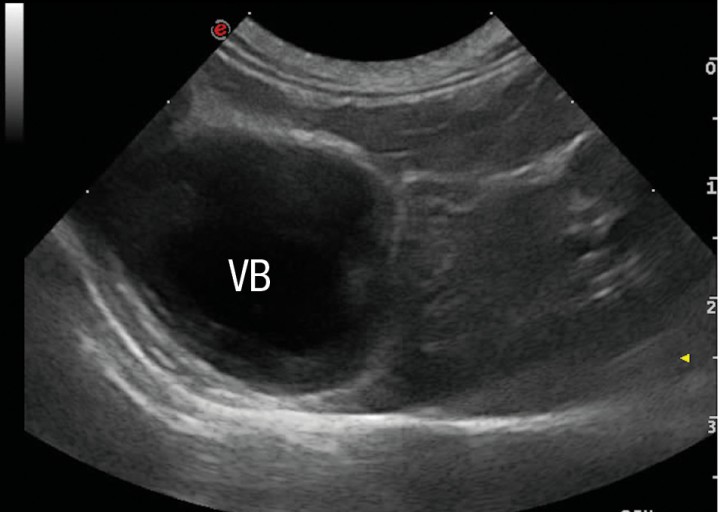

La ecografía hepática mostro un hígado de pequeño tamaño, con presencia de focos hiperecoicos y con sombra acústica (Fig. 2). Los conductos biliares mostraban distensión severa y aspecto tortuoso, manteniendo su comunicación con la vesícula biliar, sin evidencia de obstrucción en algún punto concreto de su recorrido (Fig. 3). La papila duodenal se visualizaba normal. La vena porta presentaba pequeño tamaño, flujo hepatópeto y velocidad aparentemente reducida (Fig. 4). Se evidenció la presencia de múltiples vasos de aspecto tortuoso adyacentes al riñón izquierdo (Fig. 5). Ambos riñones presentan múltiples infartos renales y focos mineralizados en la corteza, sedimento con sombra acústica en pelvis renal izquierda y presencia de cálculos en riñón derecho (Fig. 6). Pequeña cantidad de líquido libre anecoico (Fig. 7).

<p>Corte transversal del hígado. Se aprecia una disminución de tamaño del hígado. Vesícula biliar. (VB).</p>

Figura 2

Corte transversal del hígado. Se aprecia una disminución de tamaño del hígado. Vesícula biliar. (VB).

¿A nivel clínico, qué nos sugiere la presencia de un hígado de pequeño tamaño, renomegalia bilateral y urolitiasis?

Estos hallazgos suelen aparecer de forma secundaria a la reducción del flujo venoso portal al hígado. La microhepatía puede observarse en caso de hipoplasia primaria de la vena porta, hepatitis crónica o cirrosis, y la renomegalia bilateral puede verse en caso de trastorno hipertensivo portal congénito, pero la combinación de estos tres hallazgos se ha visto que tiene un valor predictivo positivo del 100% de presencia de trastorno vascular hepático.[ d’Anjou MA, Penninck DG, Cornejo L, Pibarot P (2004) Ultrasonographic diagnosis of portosystemic shunting in dogs and cat. Vet Radiol Ultrasound 45:424-437. [PubMed] ]